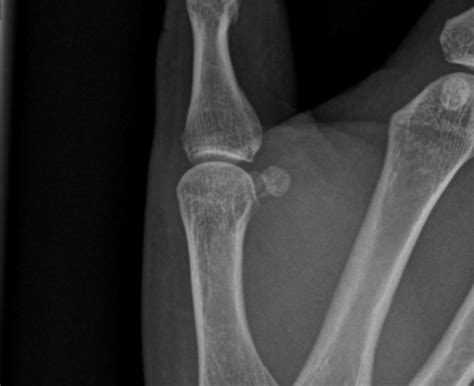

• X-Rays: X-ray images to visualize the bones and identify any fractures.